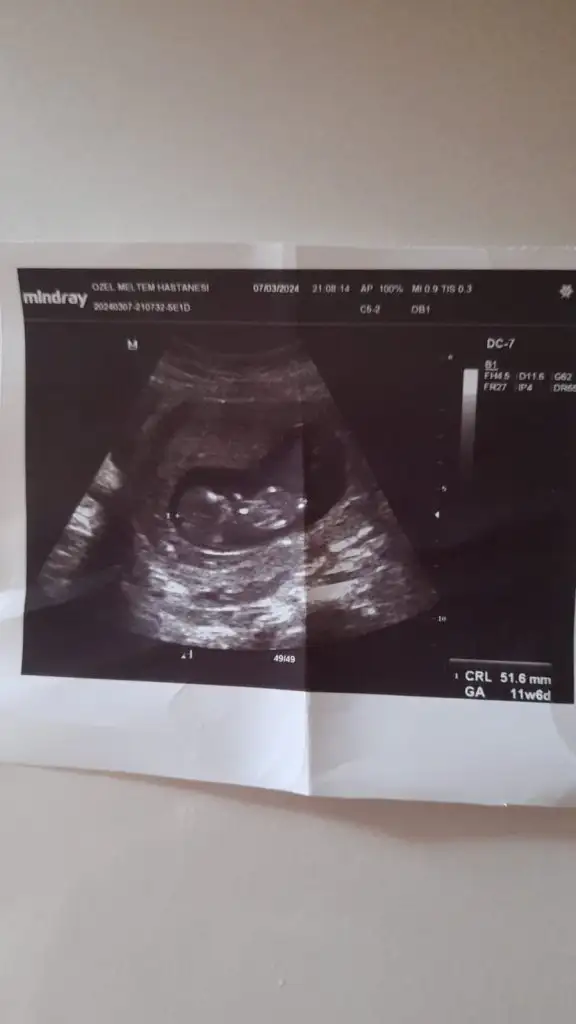

12+3 bakar mısıznz doktor net bir şey demedi

Eklentiler

• IMG_2270.webp

IMG_2270.webp

49,9 KB · Görüntüleme: 53